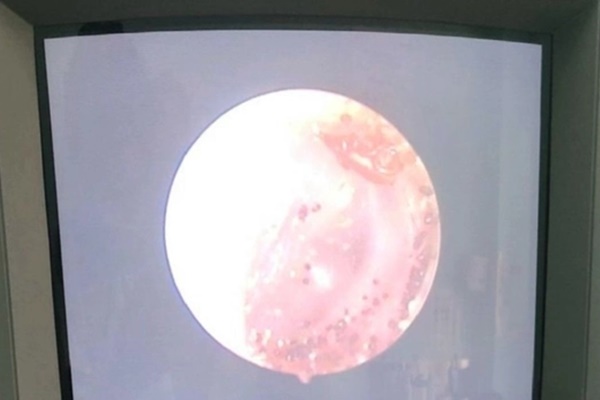

Nội soi phát hiện Ve chó trong tai bệnh nhân 13 tuổi

Khám bằng mắt thường, nhìn như có ráy đen trong tai. Tuy nhiên, tiến hành nội soi, các bác sĩ phát hiện có dị vật sống trong tai là con ve chó, đáng chú ý dị vật đang làm tổ trứng rất nhiều trong ống tai. Ngay lập tức, các bác sĩ đã làm thủ thuật và lấy toàn bộ dị vật ra ngoài, vệ sinh tai cho bệnh nhân.